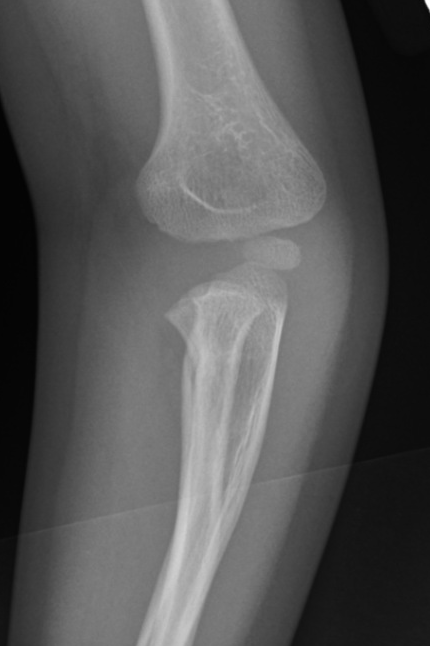

Case 2. Chronic Monteggia with deformed radial head